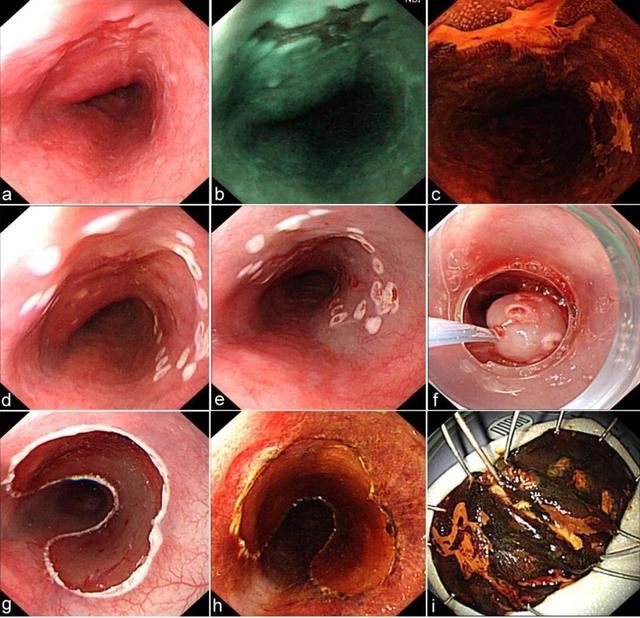

a 内镜下显示食管黏膜粗糙、糜烂,活检病理为重度异型增生;b NBI模式下病变呈深棕色;c 碘染色阳性;d 标记后;e 黏膜下注射后; f 透明帽法行内镜下黏膜切除;g 切除后创面;h 切除后重新碘染色,人工溃疡周围未见阳性病灶;i 切除的标本